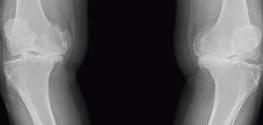

2 膝内翻。

指的就是是O型腿,管你大O小O,不管你股骨内旋或不内旋,都是膝下内翻,因为你的膝盖下侧在上图中蓝色的平面往人身体中线转向了。下图X线平片是胫骨变性造成的膝内翻,此人内侧软骨全部不见了,所以看不到空隙,他走路一定很痛很辛苦。